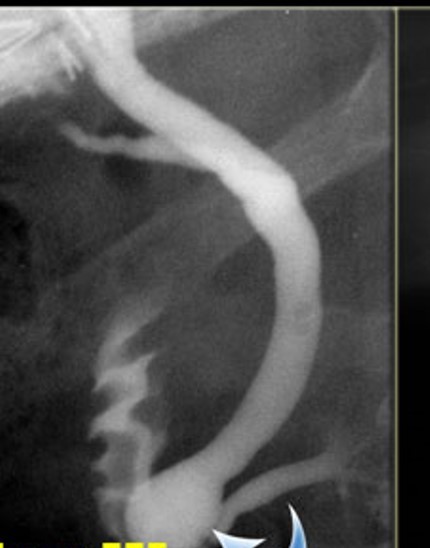

The study is compatible with dilatation of entire extrahepatic bile duct, that’s also known as a true choledochal cyst. Is the type 1 of Todani classification of bile duct cysts.

todani type I

fusiform common bile duct dilation

most common choledochal cyst

tondani type I = fusiform dilation of the CBD